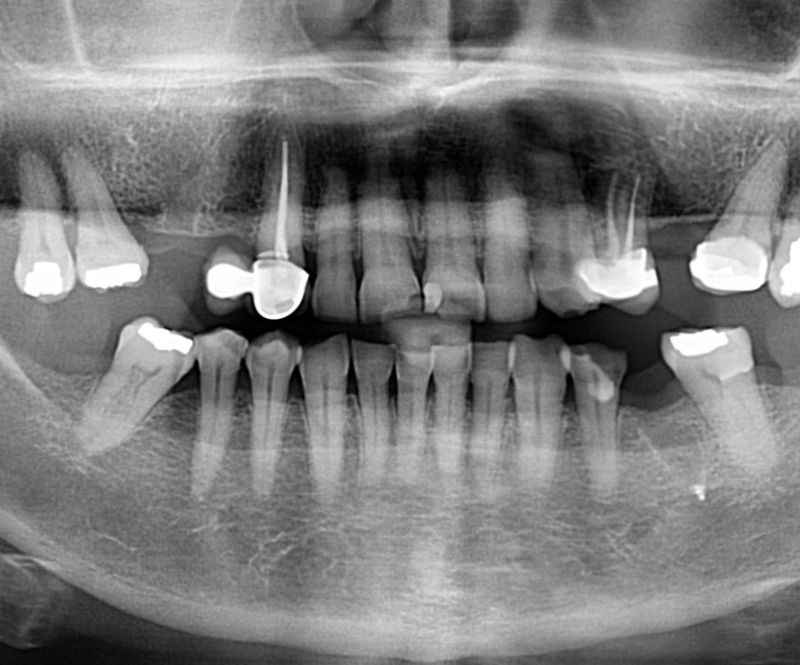

En Oral Park transformamos sonrisas con materiales de máxima calidad. En este caso, combinamos zirconio monolítico en el sector posterior y zirconio-cerámica en el anterior, logrando una estética natural y resistencia óptima.